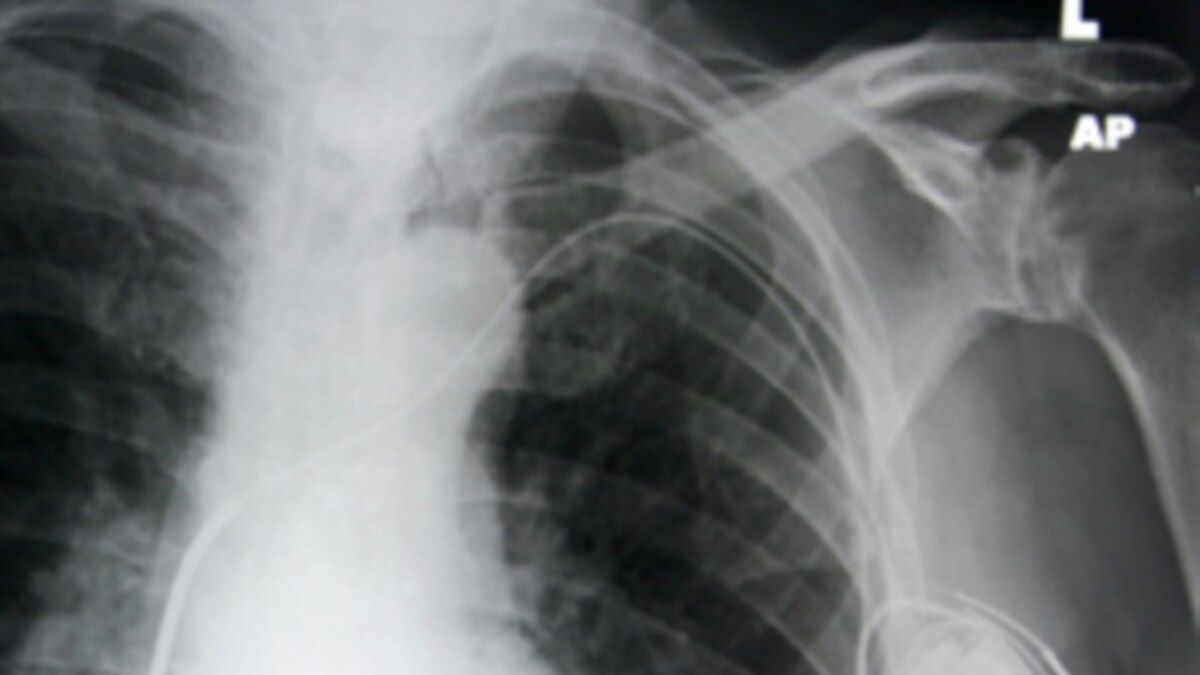

Permanent pacemaker wire infective endocarditis Emergency Medicine

Permanent pacemaker wire infective endocarditis Emergency Medicine Can A Pacemaker Affect A Hearing Aid recent studies and guidelines suggest that modern hearing aids and pacemakers can safely coexist with. However, it is crucial to consult with your healthcare. It’s a common question asked by patients who suffer from both hearing. can i wear a hearing aid with a pacemaker? A pacemaker is a device that sends small electrical impulses to the heart. Can A Pacemaker Affect A Hearing Aid.